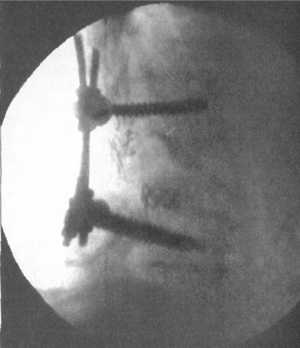

завершают костной ауто- или аллопластикой. Рану ушивают до дренажей. Пример

использования пластин с транспедикулярной фиксацией винтами представлен на рис.

6.1.

Рис. 6.1. Комбинированная стабилизация:

межделовой металлоспондинодез и транспедикулярная стабилизация |